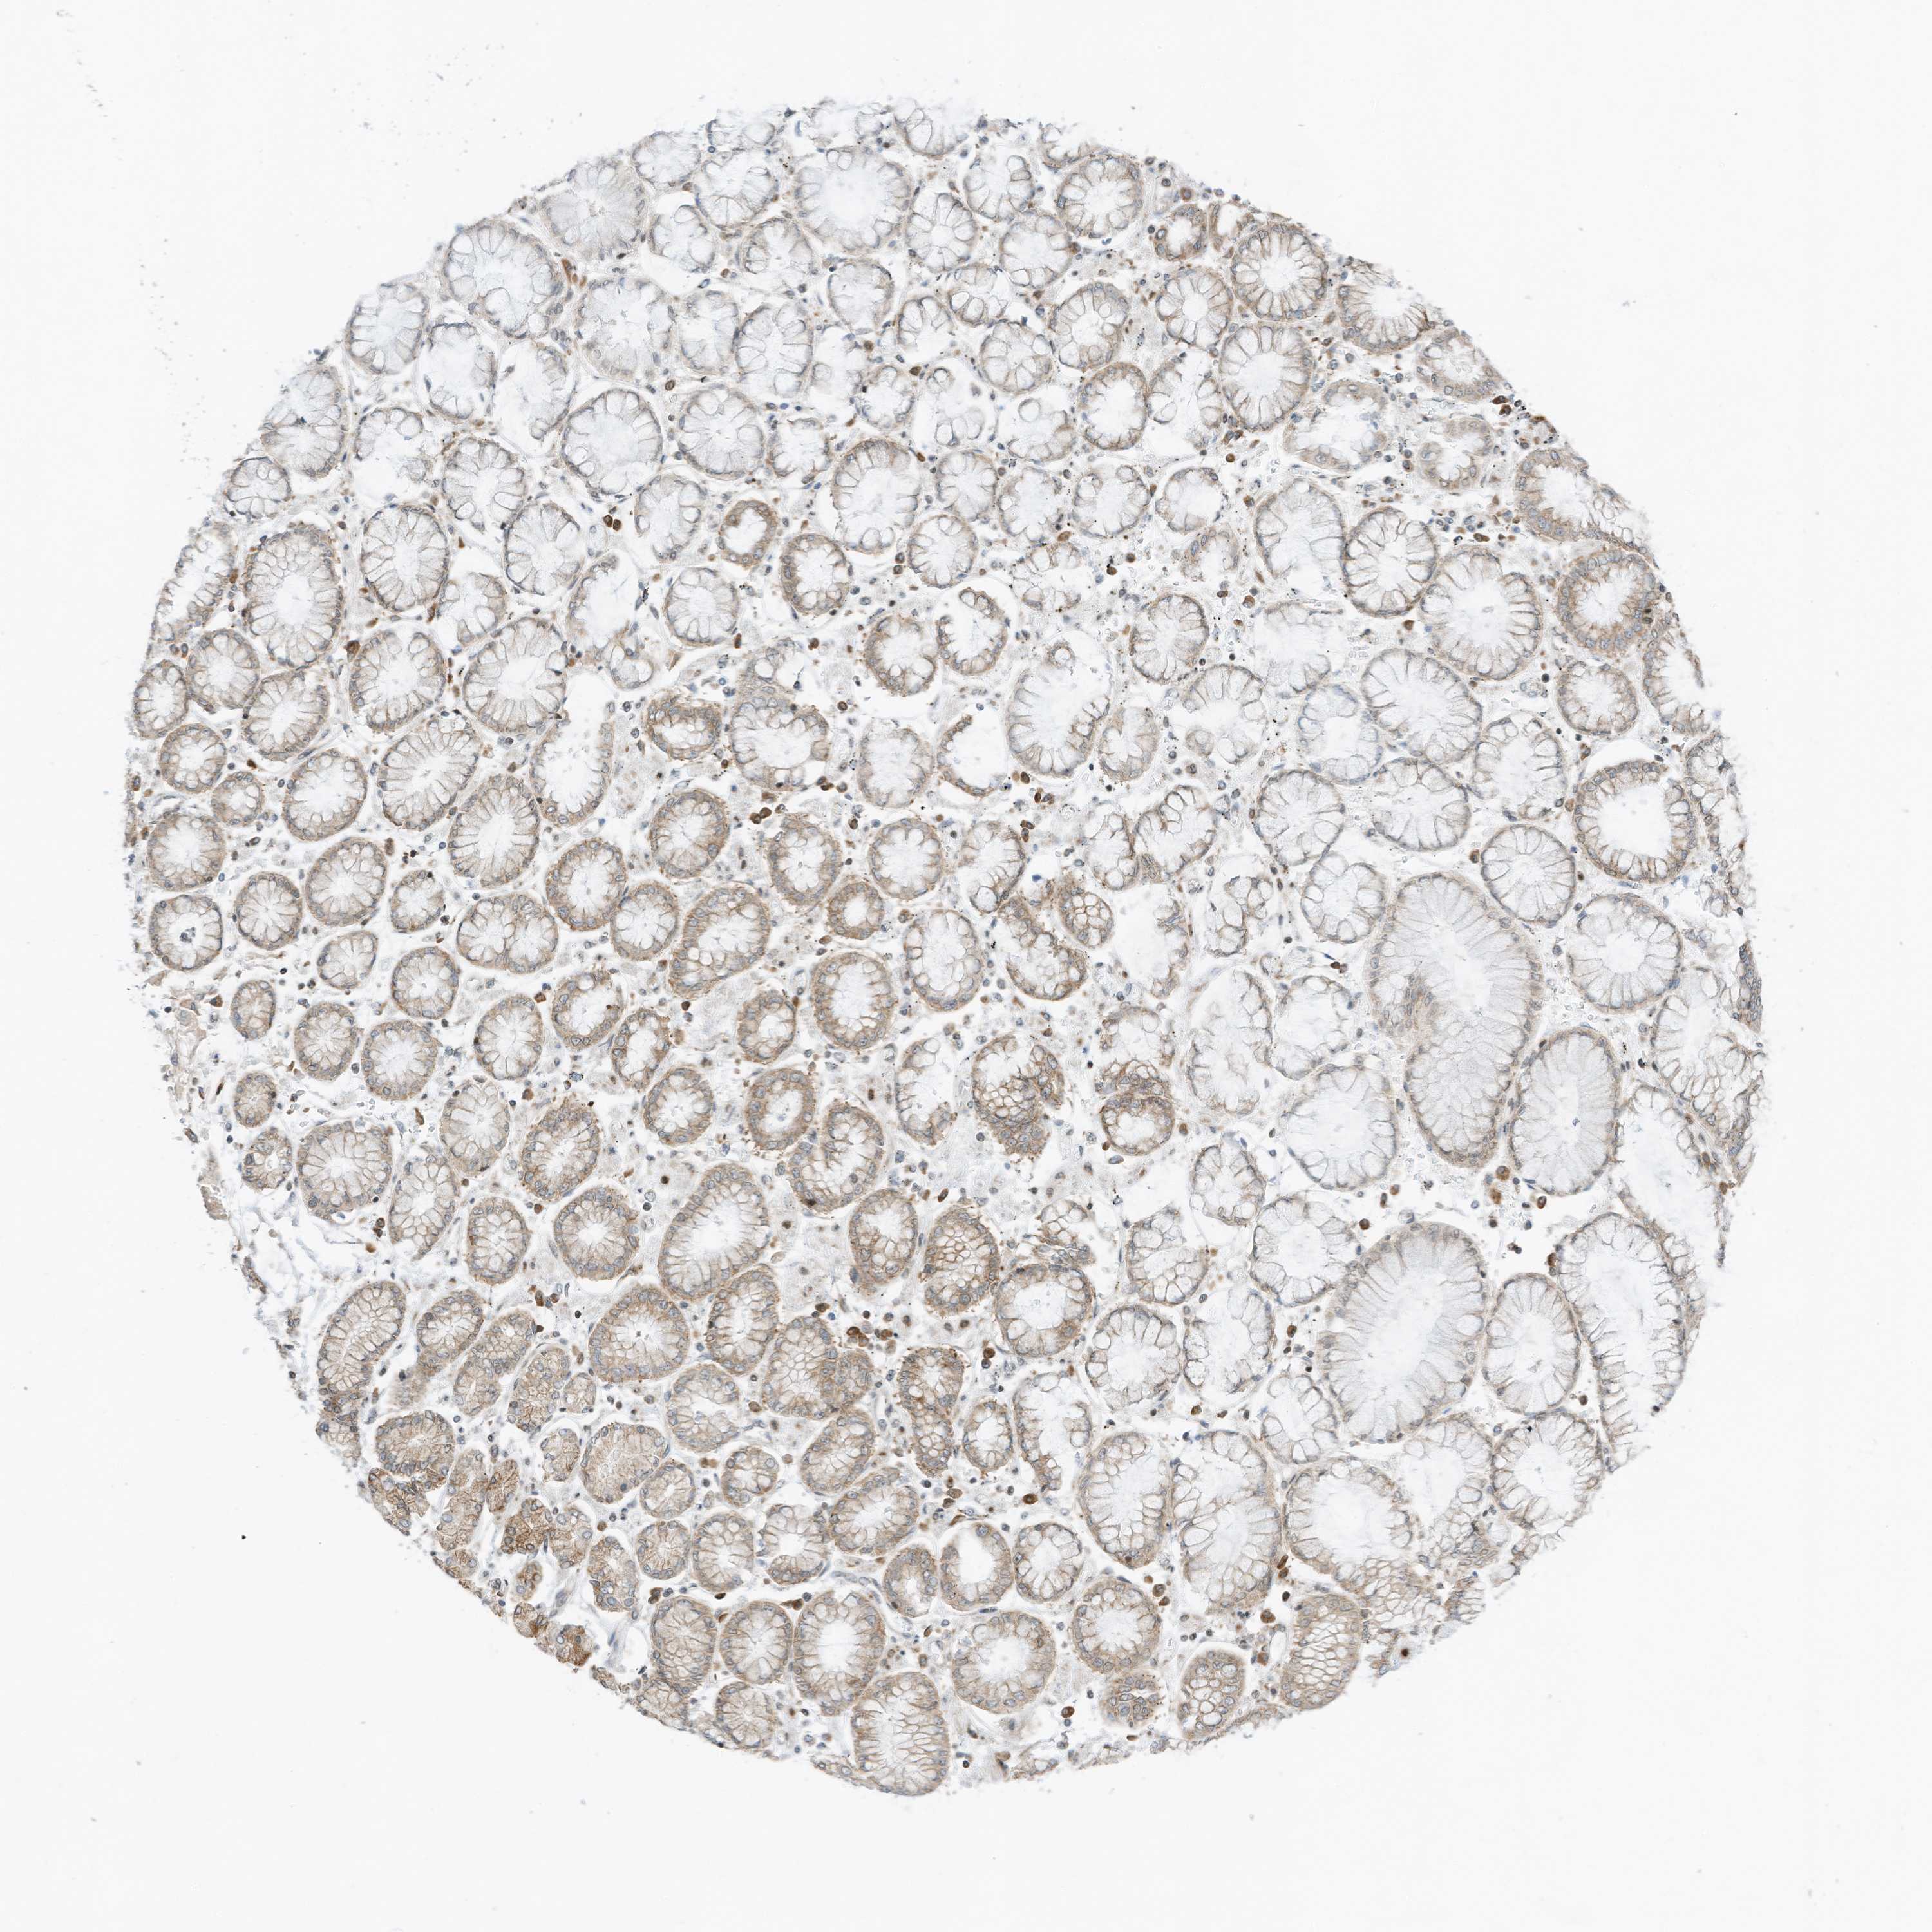

STOMACH CANCER - Protein expressioni

A mouse-over function shows sample information and annotation data. Click on an image to view it in a full screen mode. Samples can be filtered based on level of antibody staining by selecting one or several of the following categories: high, medium, low and not detected. The assay and annotation is described here.

Note that samples used for immunohistochemistry by the Human Protein Atlas do not correspond to samples in the TCGA dataset.

Antibody stainingi

Antibody staining in the annotated cell types in the current human tissue is reported as not detected, low, medium, or high, based on conventional immunohistochemistry profiling in selected tissues. This score is based on the combination of the staining intensity and fraction of stained cells.

Each image is clickable and will lead to virtual microscopy that enables deeper exploration of all samples and also displays staining intensity scores, fraction scores and subcellular localization as well as patient and tissue information for each sample.

Antibody HPA035642

Staining

High

Medium

Low

Not detected

Intensity

Strong

Moderate

Weak

Negative

Quantity

>75%

75%-25%

<25%

None

Location

Nuclear

Cytoplasmic/membranous

Cytoplasmic/membranous,nuclear

Adenocarcinoma, NOS